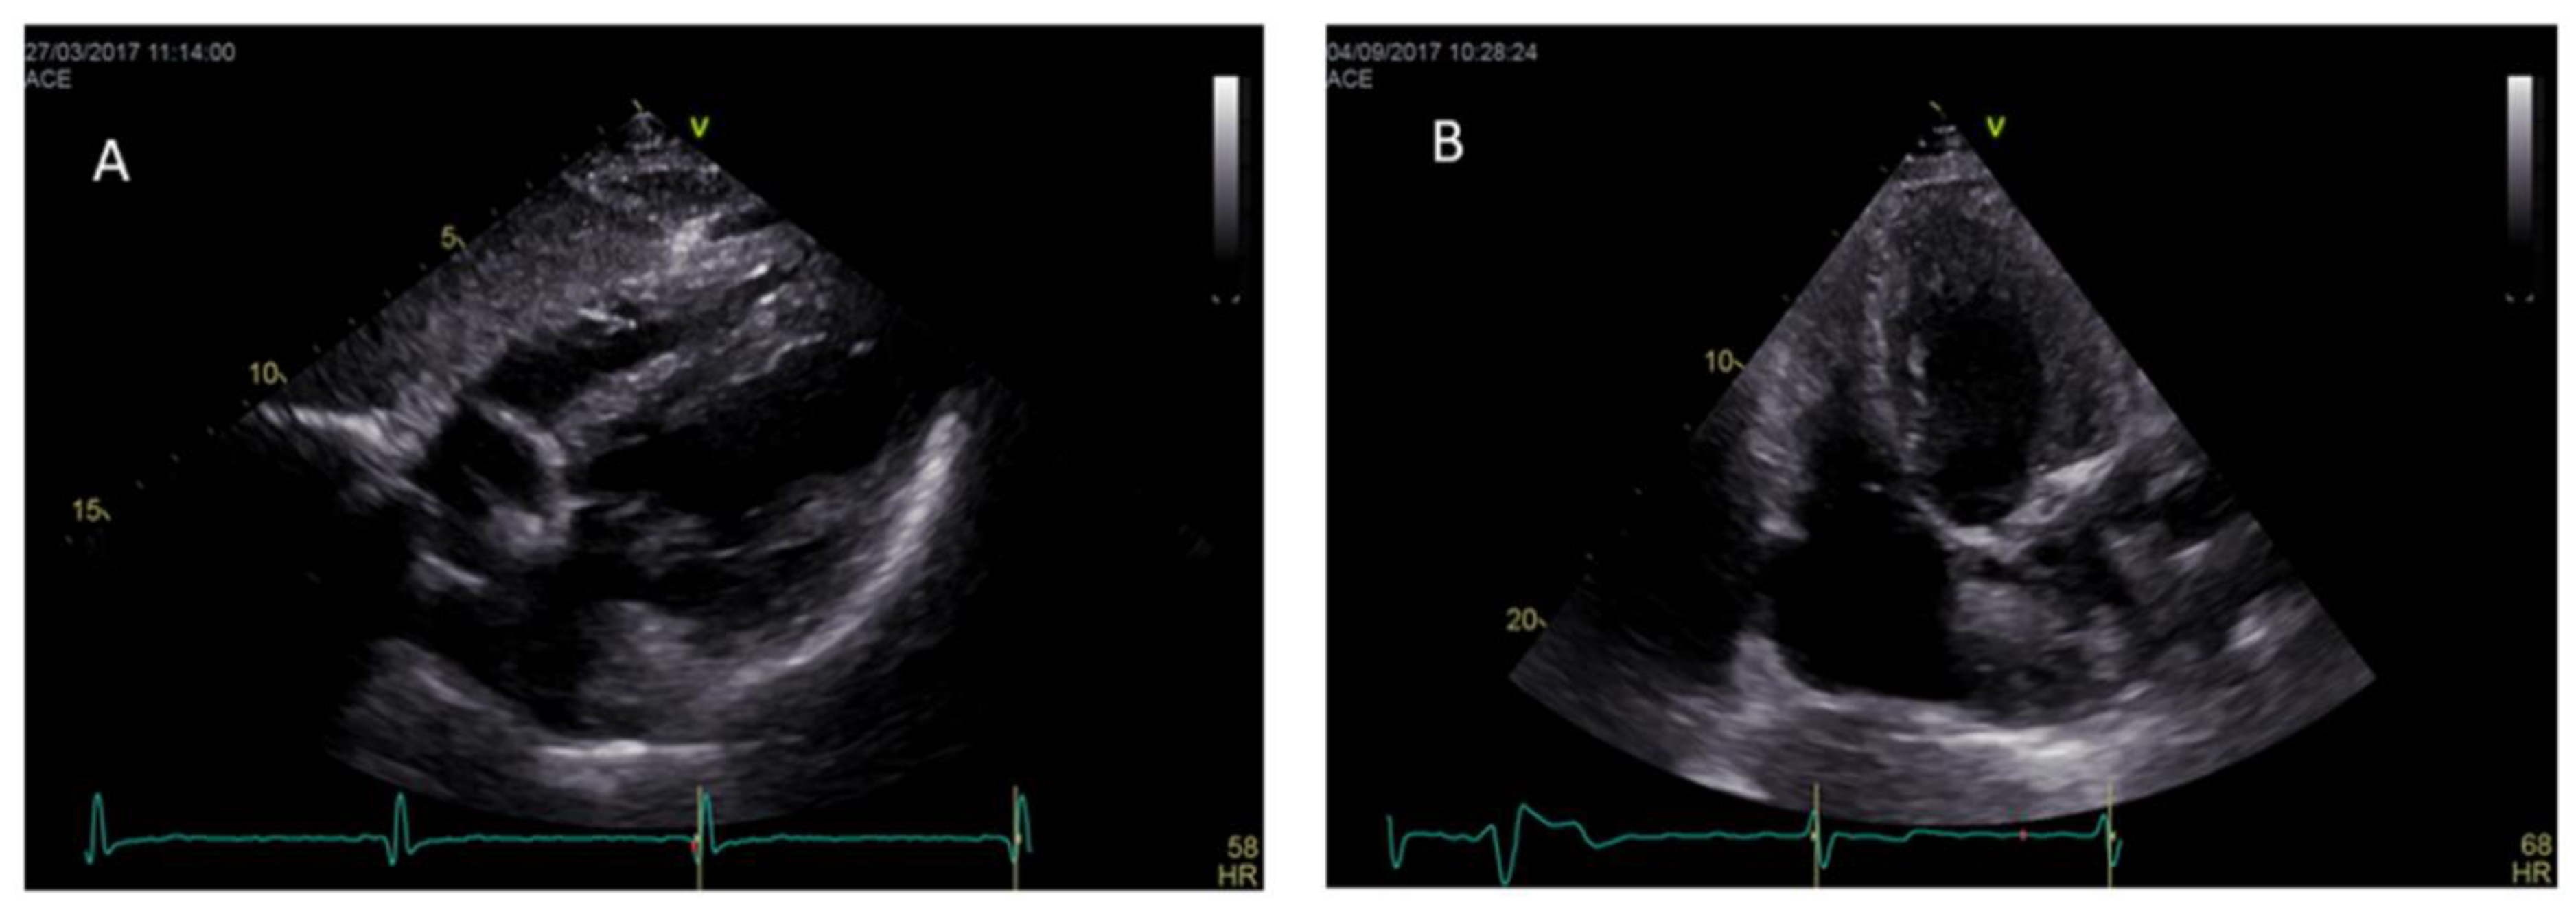

| Cine-sequences | -Measurement of LV mass, ventricular volumes, LV and RV EF, wall motion assessment | -Better quantification of LV papillary muscle mass |

- Deva, D.P.; Hanneman, K.; Li, Q.; Ng, M.Y.; Wasim, S.; Morel, C.; Iwanochko, R.M.; Thavendiranathan, P.; Crean, A.M. Cardiovascular magnetic resonance demonstration of the spectrum of morphological phenotypes and patterns of myocardial scarring in Anderson-fabry disease. J. Cardiovasc. Magn. Reson. 2016, 18, 14. [Google Scholar] [CrossRef] [PubMed]